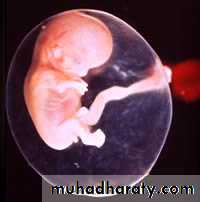

Second Week of

Development: Bilaminar Germ Disc

2nd week of Development

Growth of the bilaminar disc is relatively slow compared with that of the trophoblast; consequently, the disc remains very small .

At the end of the second week:

Trophoblast has had a period of growth- greater than the embryoblast.

The 2 layer bilaminar disc is formed and will give rise to other tissues and structures.